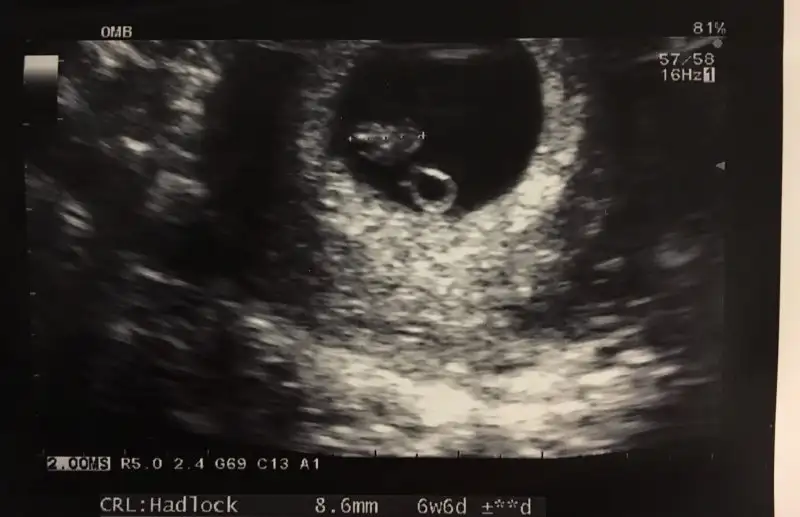

Bende pko var Cnm altı ay dur istiyorduk ovulasyon testiyle takip ettim günümü yumurtlama gününden bi gün önce ve sonra ilişki oldu öncesinde beş gün olmadı eşim yoktu ama ben le onla alakası yok tamamen nasip Cnm